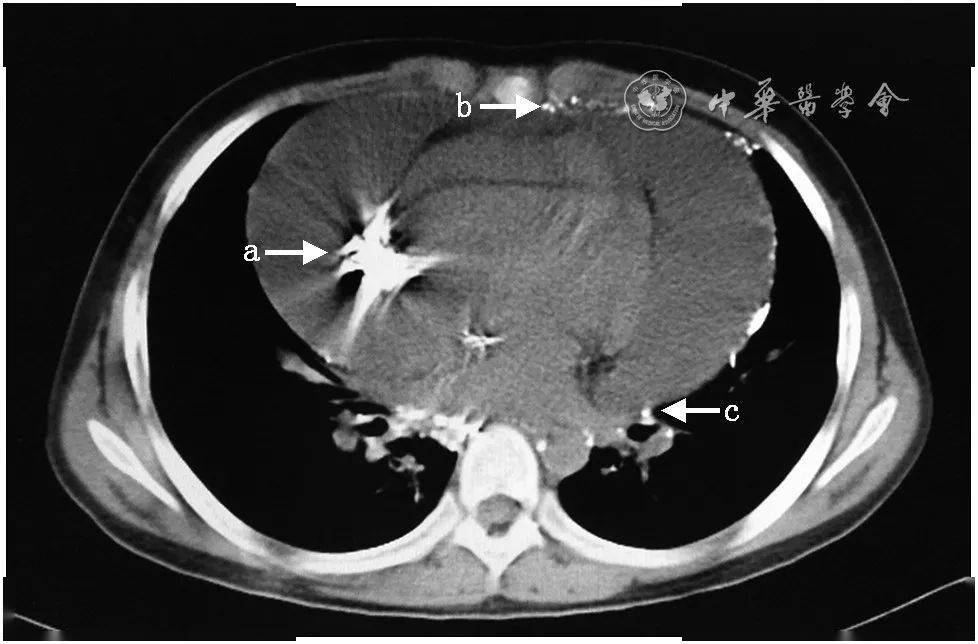

心包肿块,向心包内外生长,可见类似胸膜尾征,右心室受压变形,心包积液